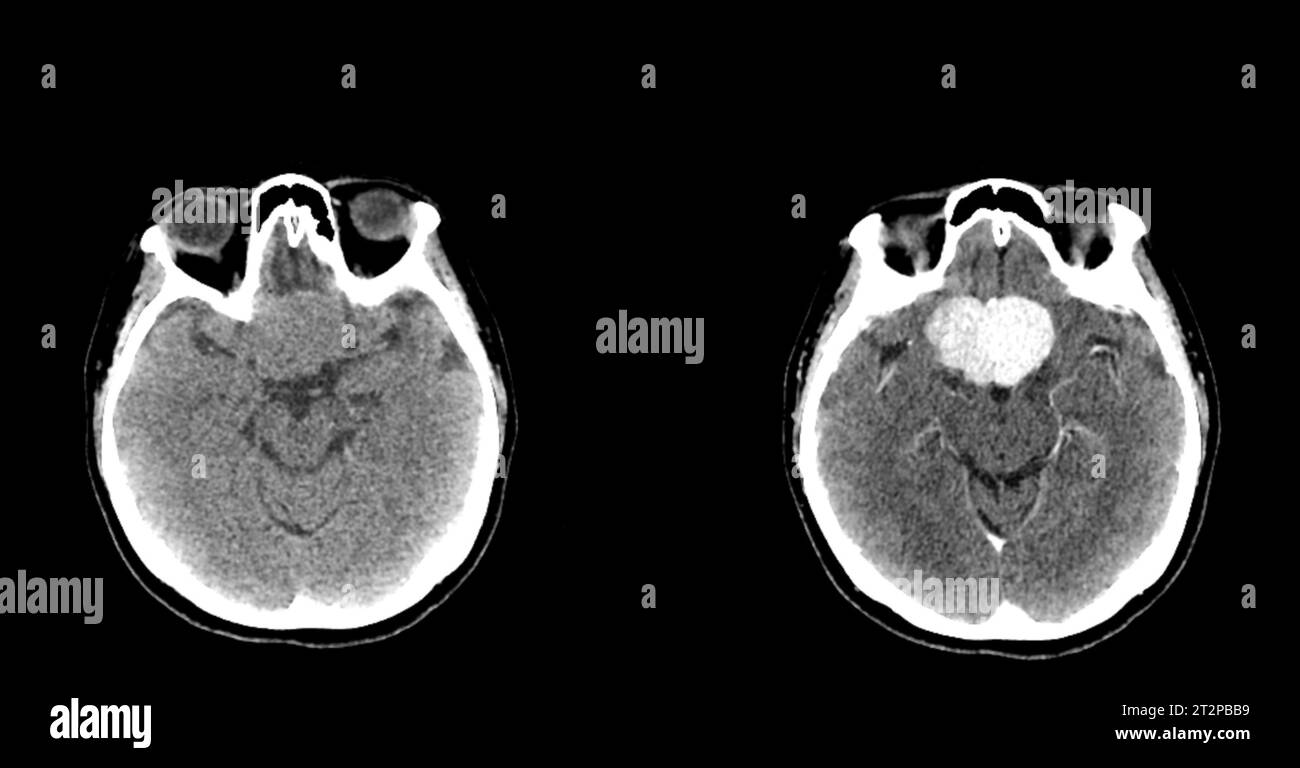

Ct Scan For Migraines . The 2 patients with severe intracranial pathology. Migraine with aura (most common type) migraine. Ahs consensus clarifies when clinicians should consider ct and mri scans for patients being assessed for migraine. Migraines have an extremely varied presentation. The other is the magnetic resonance imaging (mri). Although a ct scan, cat scan can’t definitely diagnose a migraine, it can help rule out other causes of the migraine symptoms. As a result, many types have been described 7: It can sometimes help doctors diagnose headaches. Ct scans did not show abnormalities during migraine attacks, including 2 patients with complicated migraine.

A Florida man with migraines had a CT scan which showed that his brain

A Florida man with migraines had a CT scan which showed that his brain Ct Scan For Migraines Ct scans did not show abnormalities during migraine attacks, including 2 patients with complicated migraine. The 2 patients with severe intracranial pathology. Migraines have an extremely varied presentation. Ahs consensus clarifies when clinicians should consider ct and mri scans for patients being assessed for migraine. Although a ct scan, cat scan can’t definitely diagnose a migraine, it can help rule. Ct Scan For Migraines.